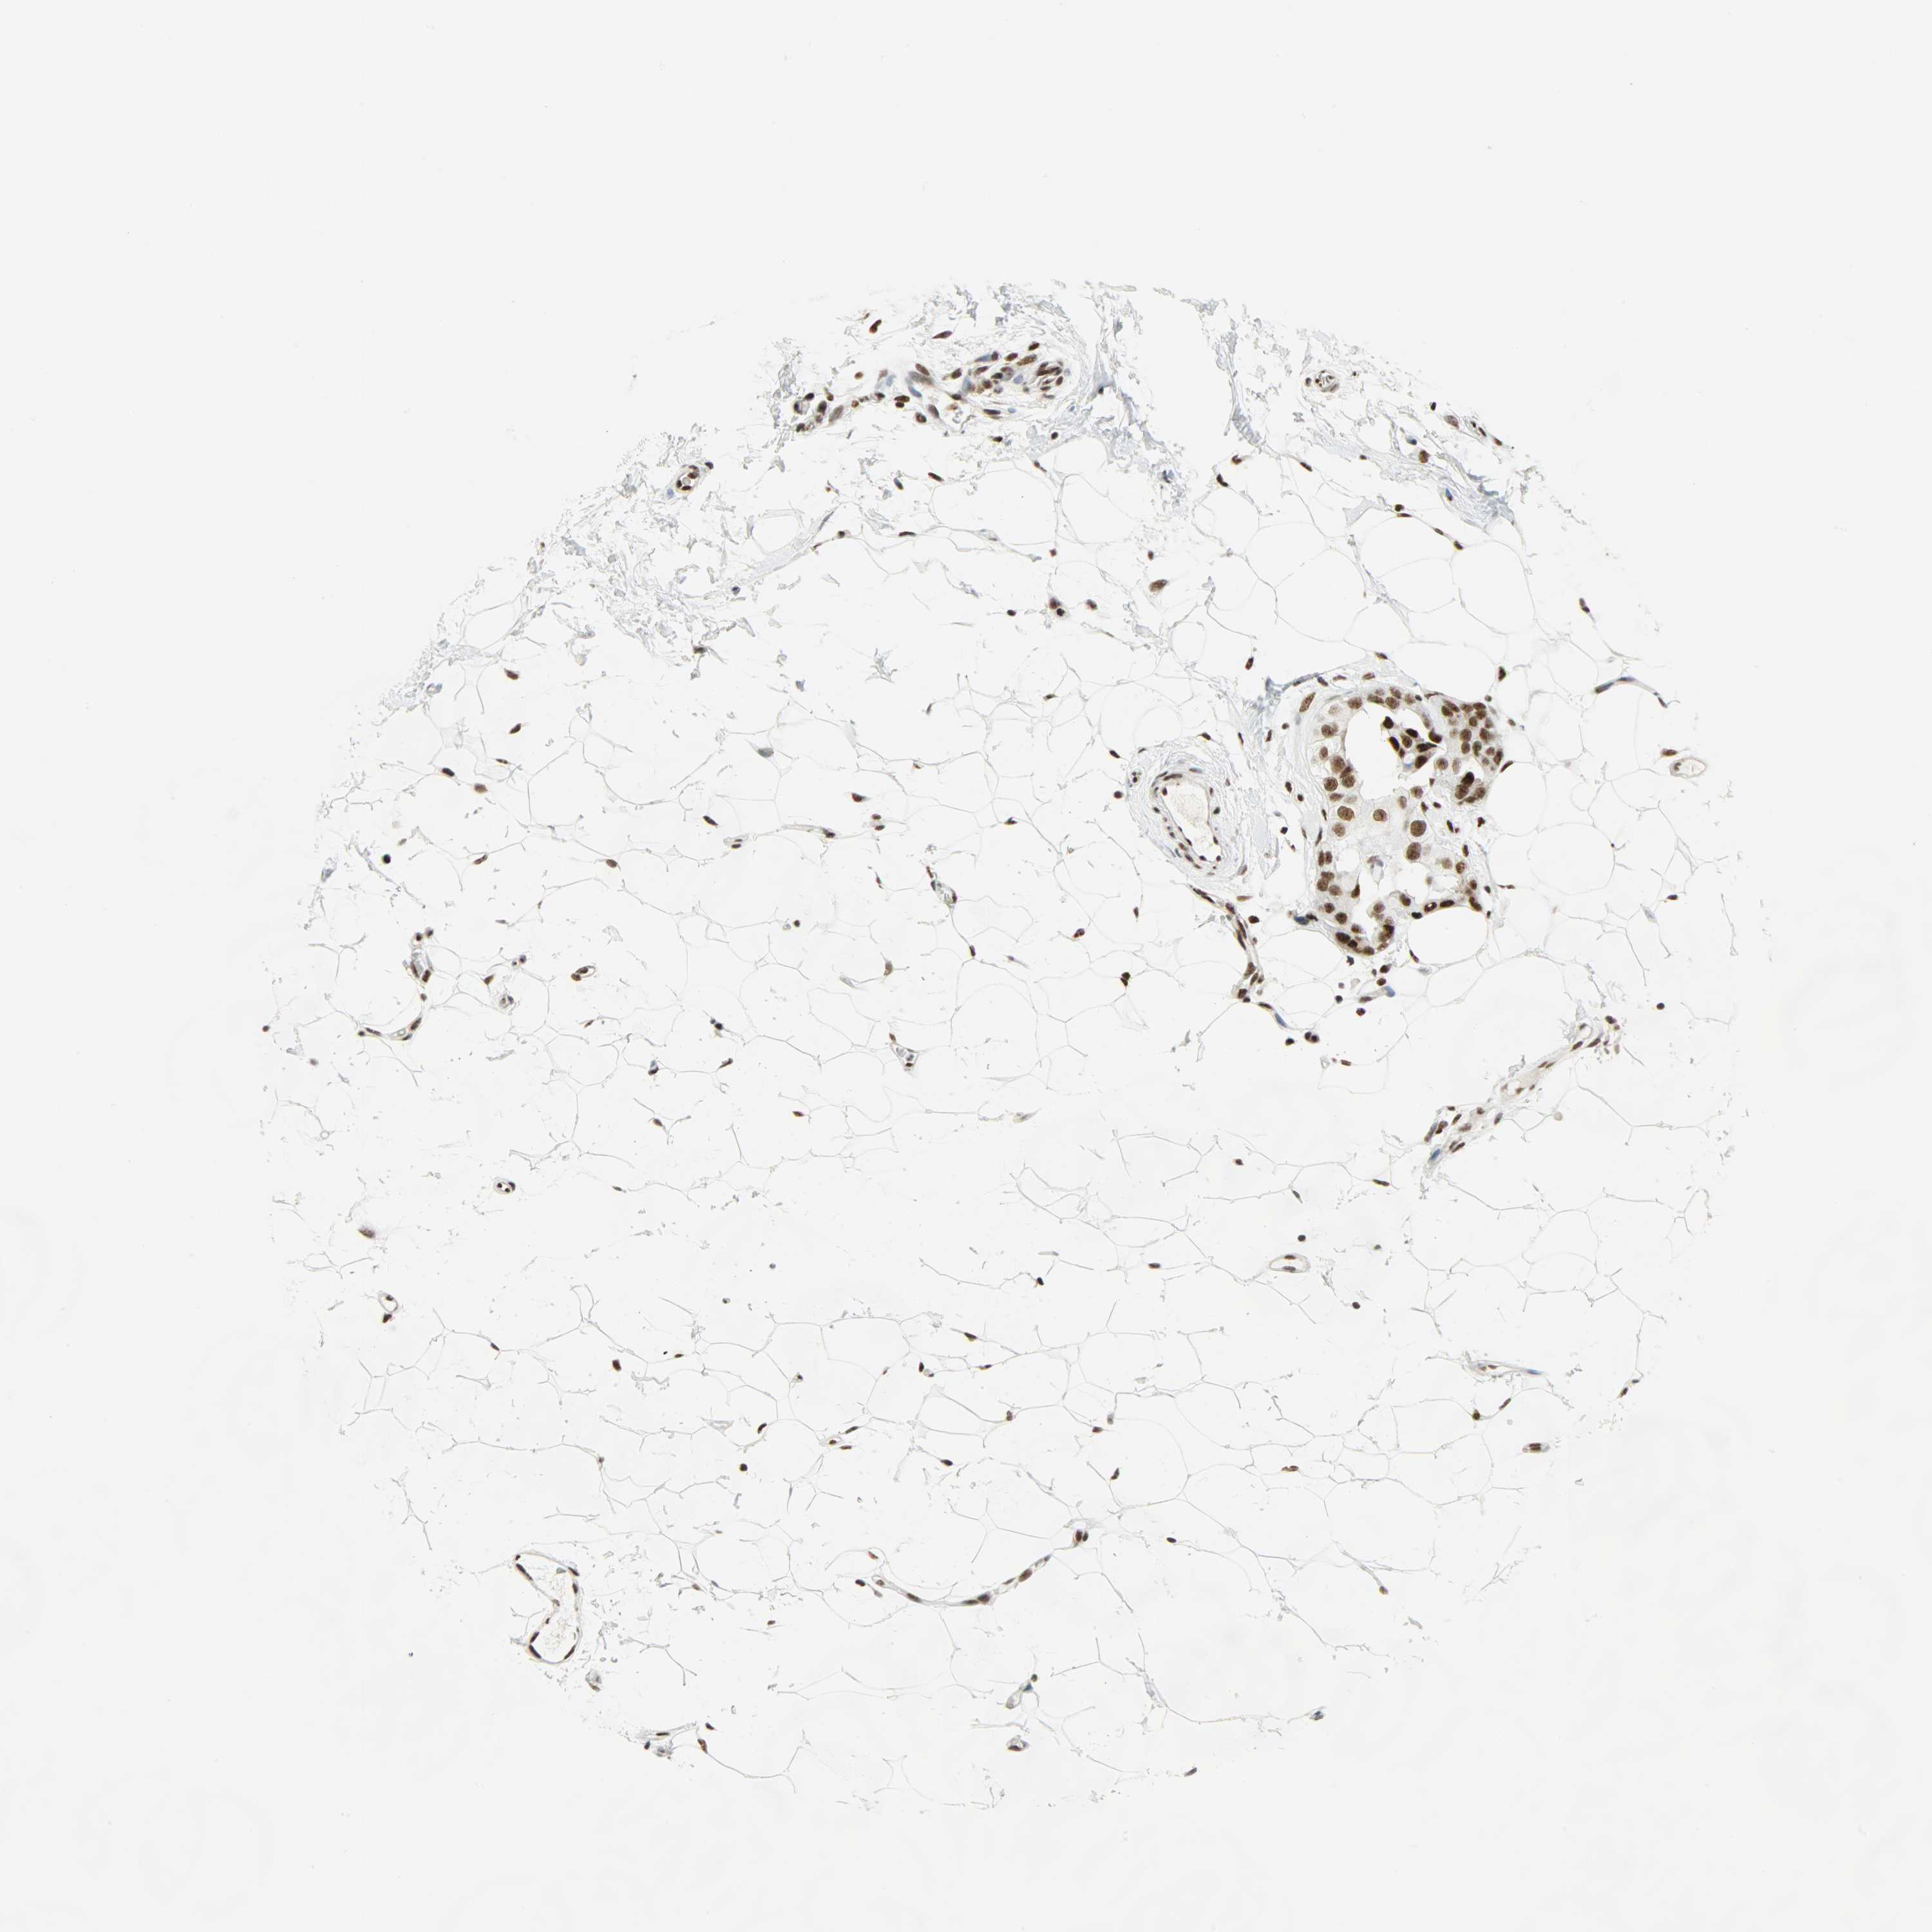

BRCA TCGA BRCA VALIDATION PROTEIN EXPRESSION